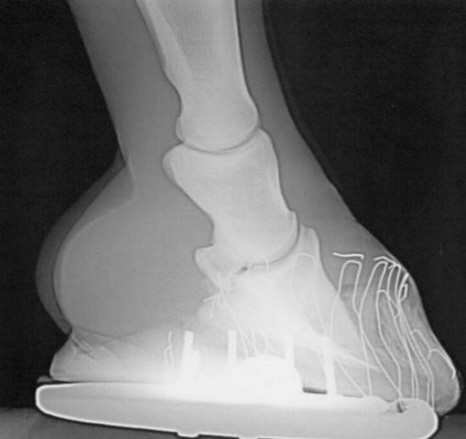

Lose Wand nach Beschlag und Hornwandaufbau